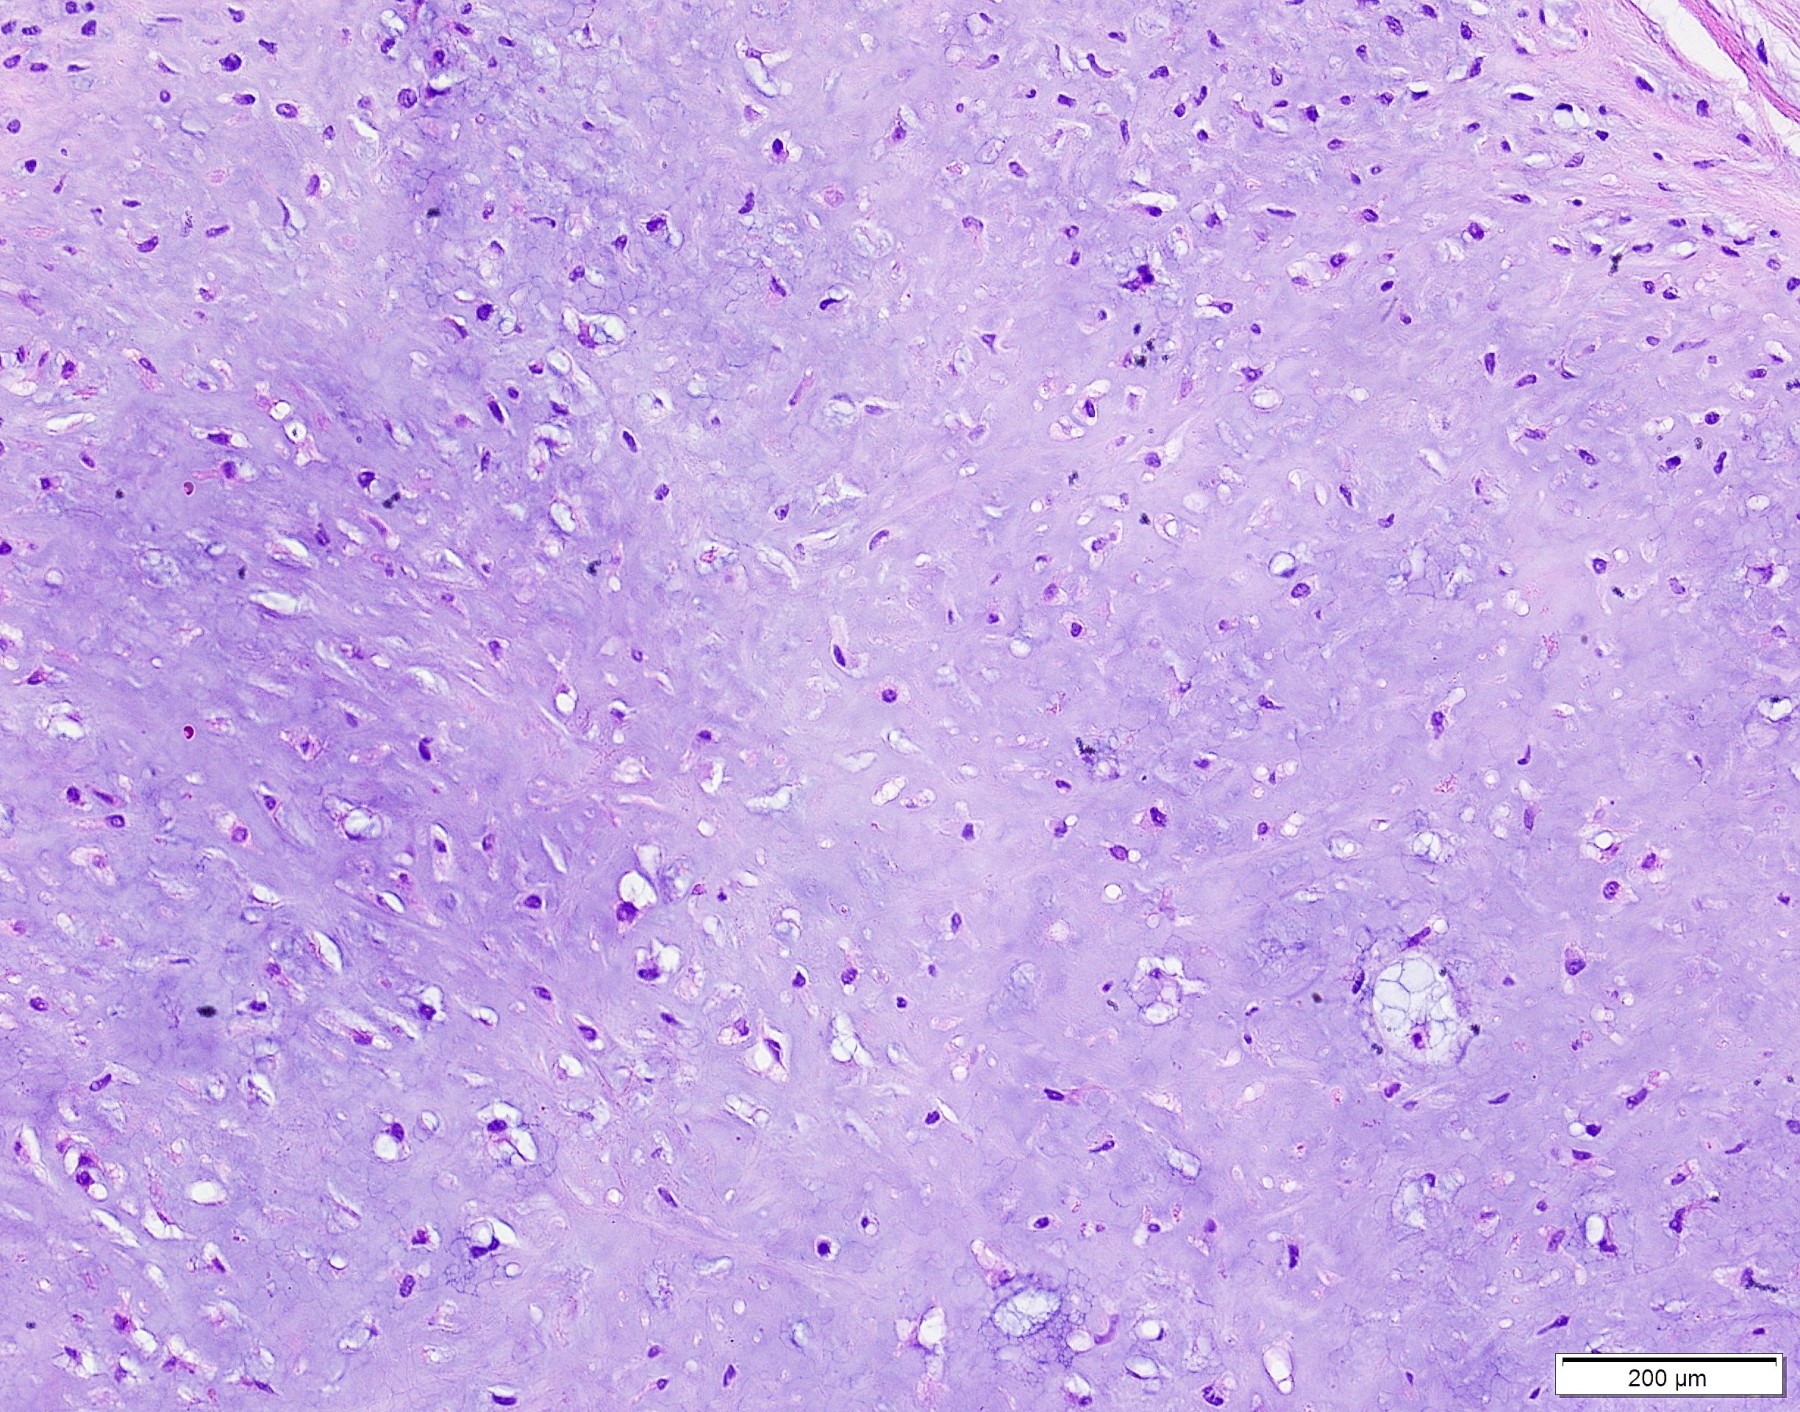

Microscopic (histologic) description

- Well demarcated tumor, often entrapped within skeletal muscle and frequently multilobulated (Am J Surg Pathol 2018;42:1297, Head Neck Pathol 2015;9:315)

- Stromal background may be hyalinized or demonstrate mucoid, myxoid or chondromyxoid areas

- Cords, strands or sheets of oval, round, fusiform or polygonal bland cells, sometimes arranged in a reticular / net-like or globoid pattern (Am J Surg Pathol 2018;42:1297)

- Myxoglobulosis-like changes have been noted (Virchows Arch 2003;442:302)

- May focally demonstrate fine calcifications, cellular atypia, necrosis, multinucleated giant cells (Am J Surg Pathol 2018;42:1297, Head Neck Pathol 2015;9:315, Oral Surg Oral Med Oral Pathol Oral Radiol Endod 1996;82:417)

- Cystic, slit-like spaces or hemorrhagic areas often noted (Head Neck Pathol 2014;8:329)

- Mitotic figures not seen (Head Neck Pathol 2015;9:315)

Microscopic (histologic) images